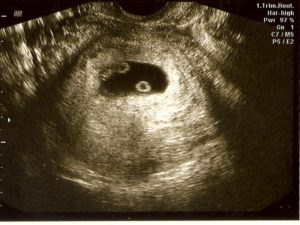

При одноплодной беременности на снимке различают темное околоплодное яйцо, которое имеет четкие, ровные границы и круглую или овальную форму. Его размер – 10 мм.

В плодном яйце заметен крошечный эмбрион (2–3 мм). На снимке он представляет собой пятно, напоминающее креветку или запятую, более светлого цвета. Если присмотреться, на картинке заметен желточный мешок (более темное пятно размером 4–6 мм) и не до конца сформировавшийся кишечник без характерных извилин.